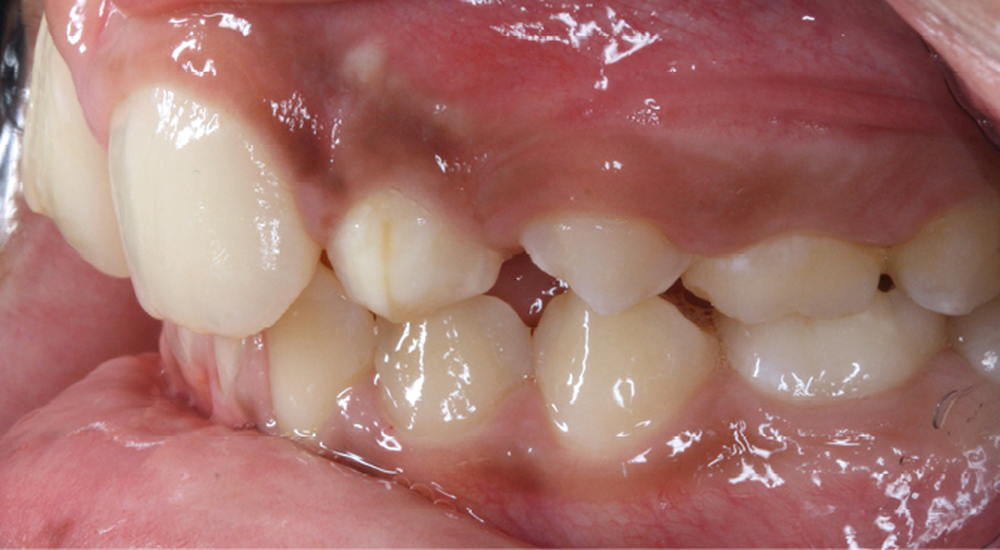

Antony, 11 ans se présente initialement pour une demande esthétique concernant ses deux incisives centrales qu’il trouve trop grosses (fig. 1a-c).

Le profil est convexe et associé à une inocclusion labiale au repos. Il s’agit d’une classe II squelettique sur un schéma facial normodivergent. Les rapports occlusaux sont de classe II bilatérale (complète au niveau molaire) avec des incisives inférieures vestibulo-versées. La 21 est géminée et la 11 vraisemblablement fusionnée avec un germe surnuméraire, sans altération de la formule dentaire. Du fait du diamètre mésiodistal fortement augmenté des incisives centrales, et du manque de place à l’arcade maxillaire qui en découle, les 12 et 22 sont en inversé d’occlusion en palato position. Les 53 et 63 sont persistantes sur l’arcade avec une inclusion en transposition incomplète de la 13, dont la cuspide se situe entre la racine de la 12 et celle de la 11 résorbée (fig. 1d-g).